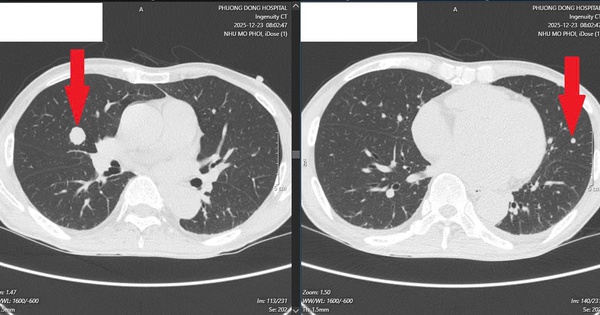

Ung thư lan khắp gan, phổi sau 6 tháng uống chanh muối để tự “chữa lành”

Rơi vào tuyệt vọng khi biết mình mắc ung thư trực tràng di căn gan, bệnh nhân 68 tuổi đã từ chối điều trị bằng y học hiện đại để về nhà tự “chữa lành”.